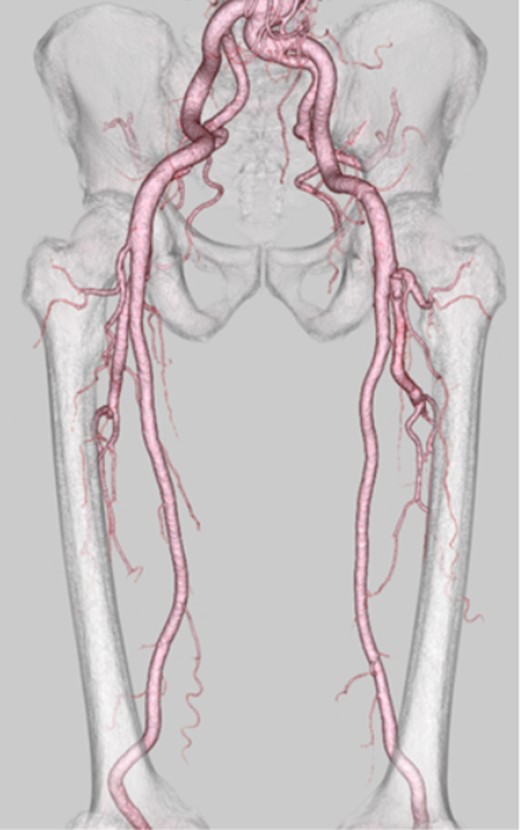

Following surgery, the patient's symptoms improved gradually. A follow-up multidetector computed tomography scan showed good blood flow in the graft, superficial femoral artery and popliteal artery (Fig. 3). The patient had an uneventful postoperative recovery and was discharged without complications.

A follow-up multidetector computed tomography scan showed good blood flow in the graft, superficial femoral artery and popliteal artery.